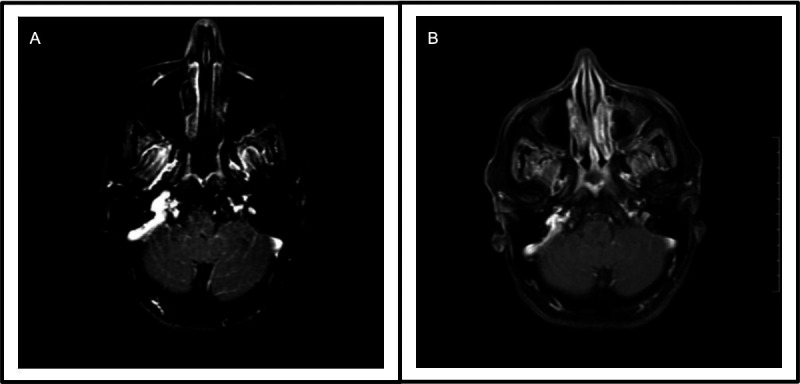

Results: We described the clinical, microbiological, radiological and serological features of five patients with a TBM-like presentation eventually diagnosed with MOG-associated meningitis. Symptoms included headache, vomiting, visual impairment and weakness. Three patients showed normal MRIs and two patients showed MRI findings consistent with demyelination. Serum MOG antibody testing was positive only on serial testing of all five patients. The final diagnosis was MOG-associated meningitis in two patients and MOG-associated meningoencephalitis in three patients.

Abstract Image